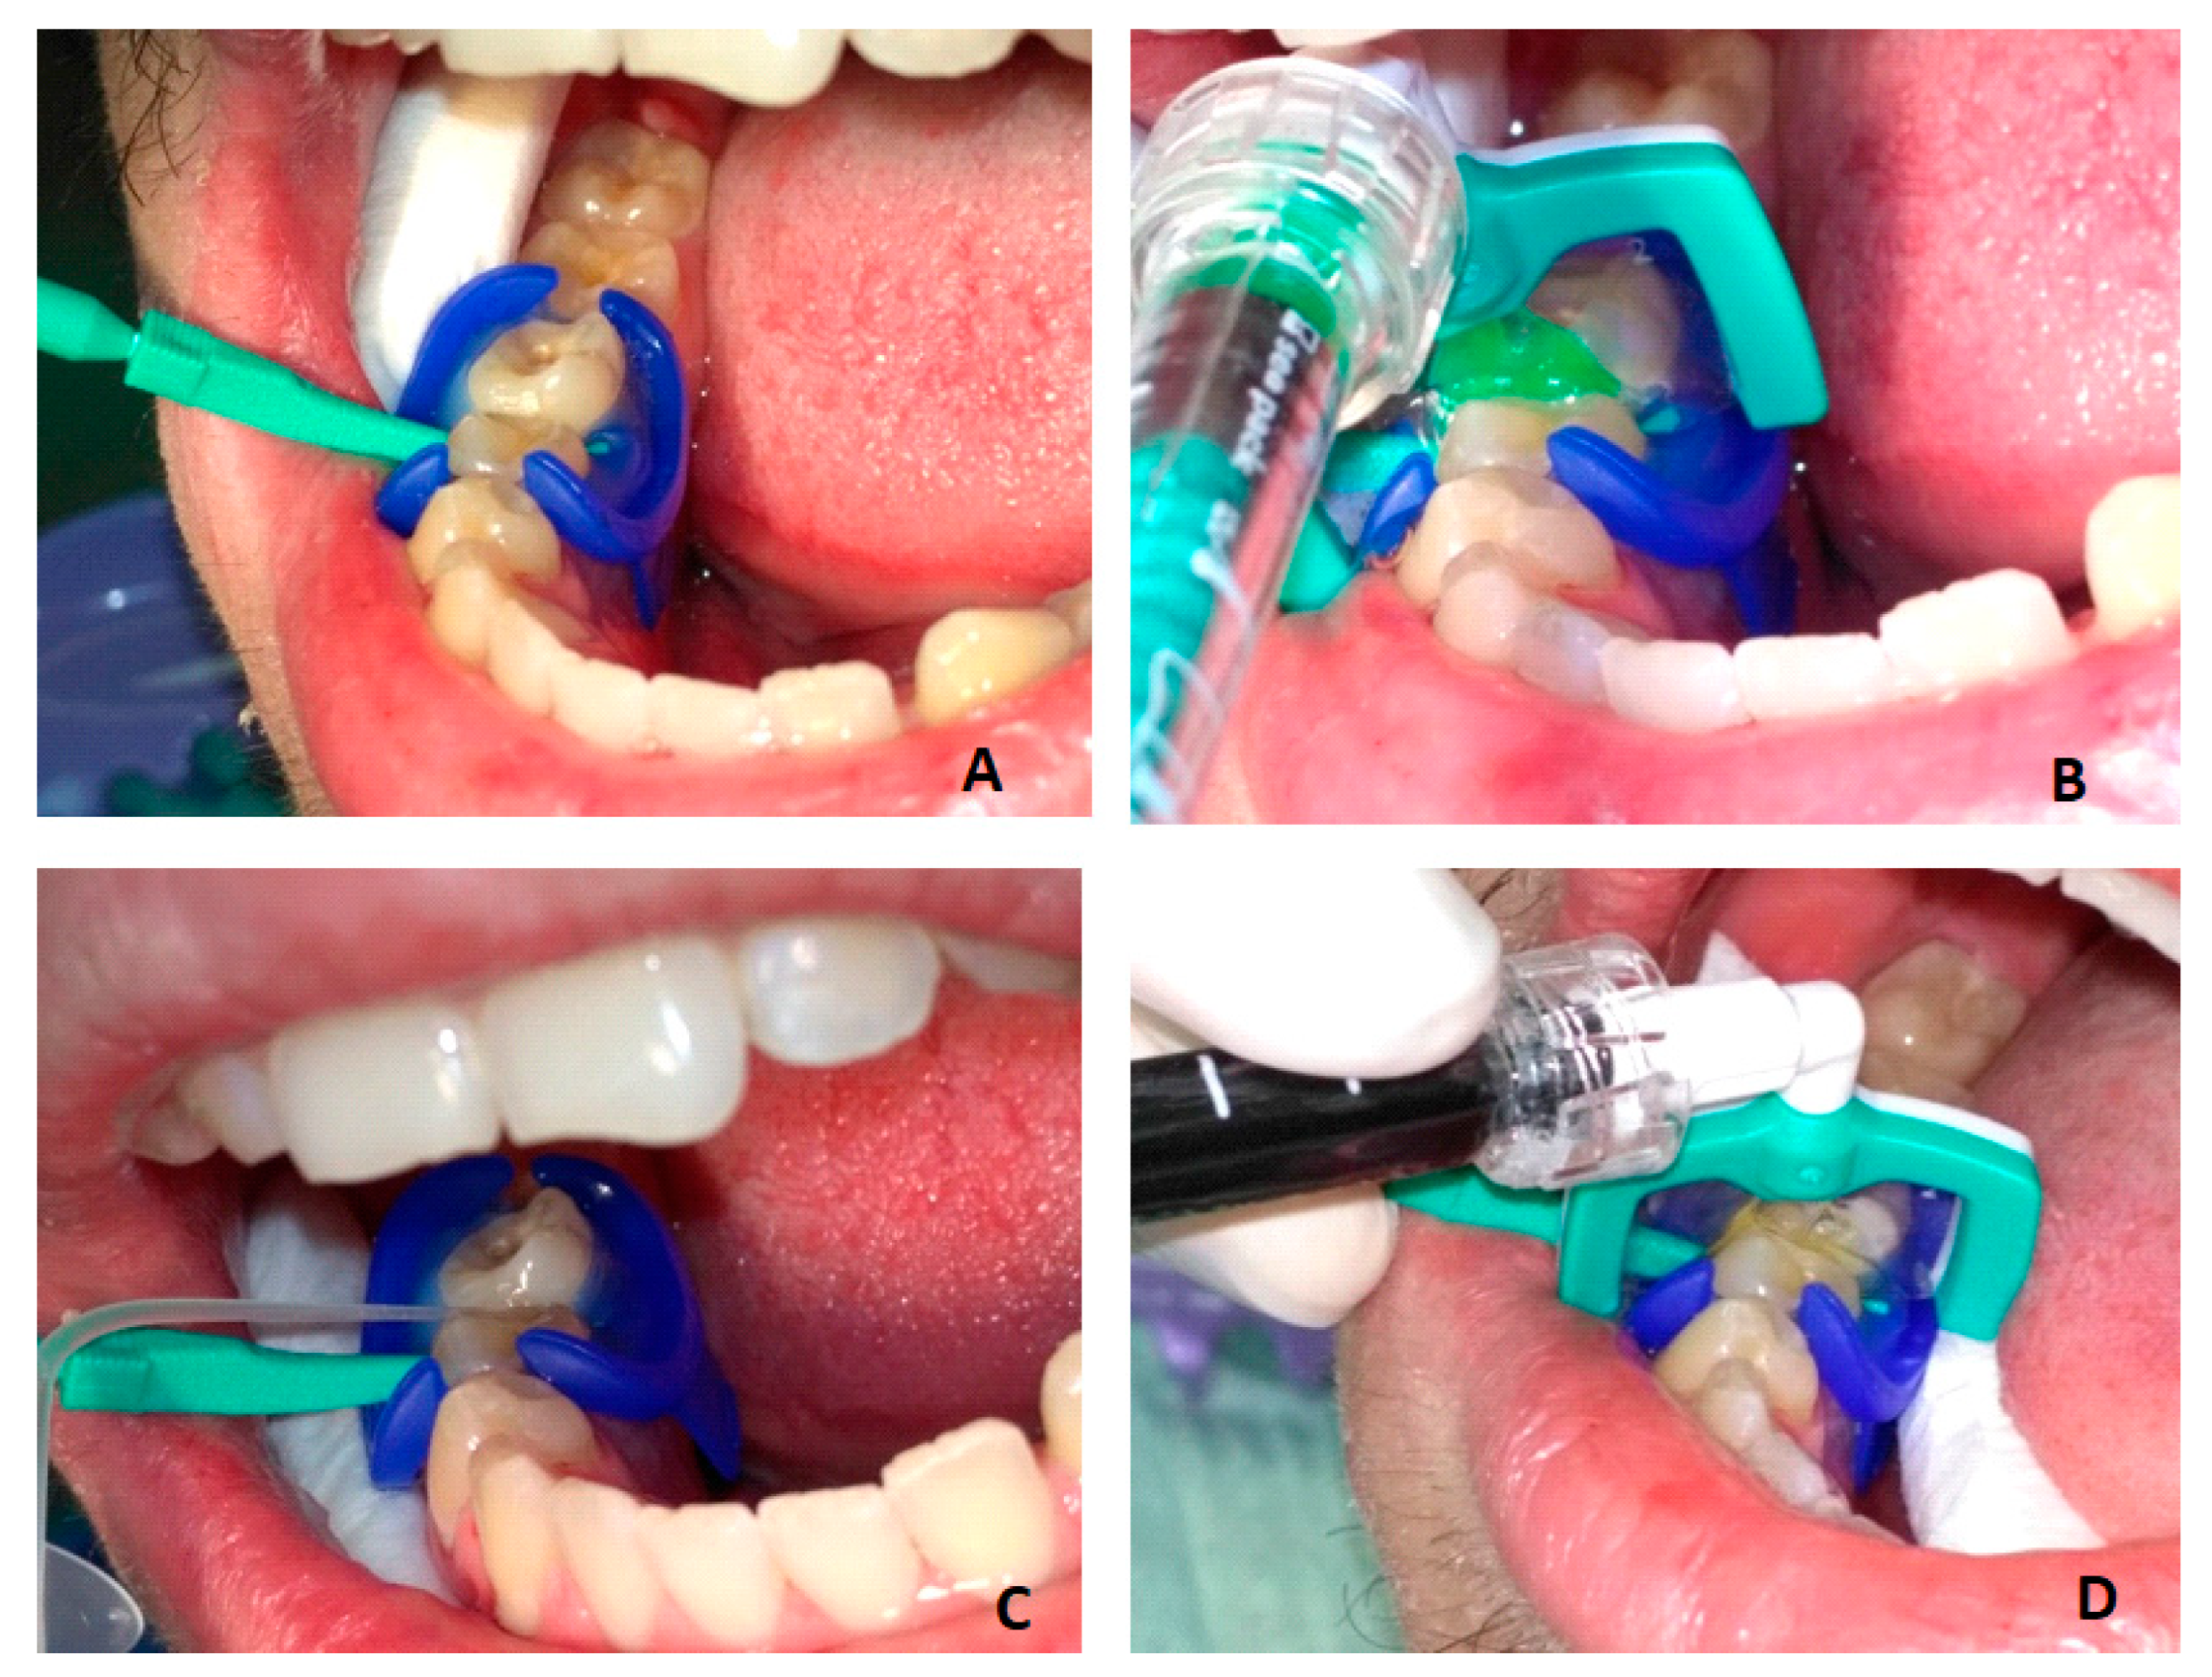

The infiltration protocol included (Figure 1):

• cleaning the tooth and isolating it with a rubber dam (MiniDam, DMG, Germany), placing a wedge (included in Icon Proximal, DMG, Germany) to separate the teeth;

• etching the tooth surface—Icon Etch (15% HCl) for 2 min;

• rinsing with water for 30 s and drying;

• application of Icon Dry (99% ethanol) for 30 s, followed by air drying;

• application of Icon Infiltrant (TEGDMA) for 3 min, removal of excess and light-curing for 40 s;

• reapplication of Icon Infiltrant for 1 min, followed by light-curing for 40 s;

• polishing.

Figure 1. Resin infiltration: (A) tooth isolation and separation; (B) etching with 15% hydrochloric acid—Icon Etch for 2 min; (C) drying with pure alcohol—Icon Dry for 30 s; (D) infiltration with Icon Infiltrant for 3 min, light-curing and second infiltration for 1 min.